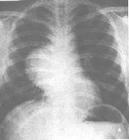

非結(jié)核性分枝桿菌系指分枝桿菌屬中,除結(jié)核分枝桿菌復(fù)合群(人型、牛型、非洲型和田鼠型結(jié)核分枝桿菌)和麻風(fēng)分枝桿菌以外的分枝桿菌,由NTM引起的疾病稱為非結(jié)核性分枝桿菌病。近年來(lái)由于檢出率逐漸增多,相應(yīng)的對(duì)其引起的各種疾病的認(rèn)識(shí)也在逐漸提高。非結(jié)核性分枝桿菌中大多數(shù)為腐物寄生菌,毒力低,屬于條件致病菌。非結(jié)核性分枝桿菌病的癥狀可有肺內(nèi)、肺外之分,肺外感染可涉及皮膚、骨骼和淋巴結(jié)等。

- 常見(jiàn)癥狀:咯血、咳嗽、咳痰、淋巴結(jié)腫大、發(fā)燒、胸痛、呼吸困難、消瘦、乏力、周身不適、盜汗 、貧血